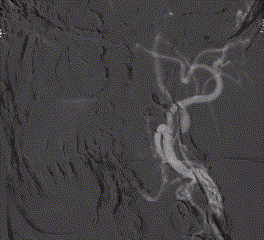

头颈联合CTA

-- 左侧颈内起始部重度狭窄,低密度斑块;右侧颈内及右侧椎动脉起始部中度狭窄;冠脉多发狭窄